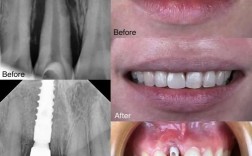

正畸前的准备是成功的关键,初次面诊时,医生会进行全面口腔检查,包括拍全景片、头颅侧位片、取牙齿模型等,以判断牙齿拥挤程度、骨骼关系及是否存在牙周问题,随后医生会与患者及家长沟通方案,明确是否需要拔牙、种植支抗等,并详细说明矫正周期(通常1.3-2.5年)、费用构成(含矫治器、复诊、保持器等)及注意事项,建议选择正规医疗机构或口腔医院的正畸科,确保医生具备专业资质,可通过查看案例、患者评价等方式综合判断。